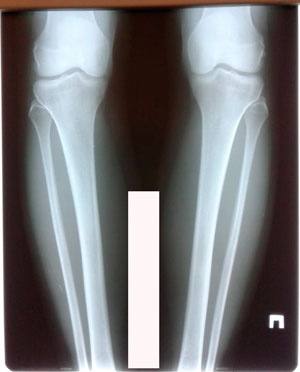

Дата операции - 04.06.2020

Дата снятия аппаратов 13.10.2020

image-04-06-20-04-35-4.jpg

image-04-06-20-04-35-2.jpg